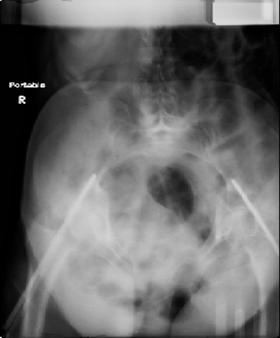

injuries are limited to the pelvis. left rami open and visible in a 10cm vertical laceration just lateral to left labia majora. wound is grossly clean. no vaginal and no urinary issues. CT scan shows widening of both SI joints anteriorly but I think this is vertically stable pattern.

so the question is what next operatively if anything? concerns are infection, nonunion anteriorly and possible incompetence of the pelvic floor which may lead to prolapse issues. right rami are comminuted and plating may entail ilioinguinal approach to extend plate laterally to right iliac wing. retrograde screw up right rami is an option but I am not convinced it will add much. adding SI screws very doable, but major concern is restoring anterior ring. so far wound is clean and closed over a drain, and I have no plans to open it back up and wash again.

maintaining pelvic alignment in ex-fix in 70 yo female for any length of time may be challenging.